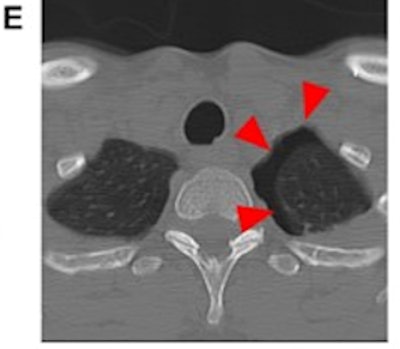

Case 3: A 49-year-old female patient was suspected to have been pushed by her partner, resulting in a fall against a bathtub. Caudal slices of a cervical spine CT showed incidental traumatic pneumothorax on the left side (arrowheads) as a result of rib fractures (not illustrated), but no pathology of the cervical spine (E). The police were informed. IPV was self-reported after questioning by medical professionals in these cases; however, we have no information on the outcomes of the police investigations on the alleged attacks.Matoori and colleagues acknowledged that talking to suspected victims of intimate partner violence can be challenging. They proposed a three-part protocol: